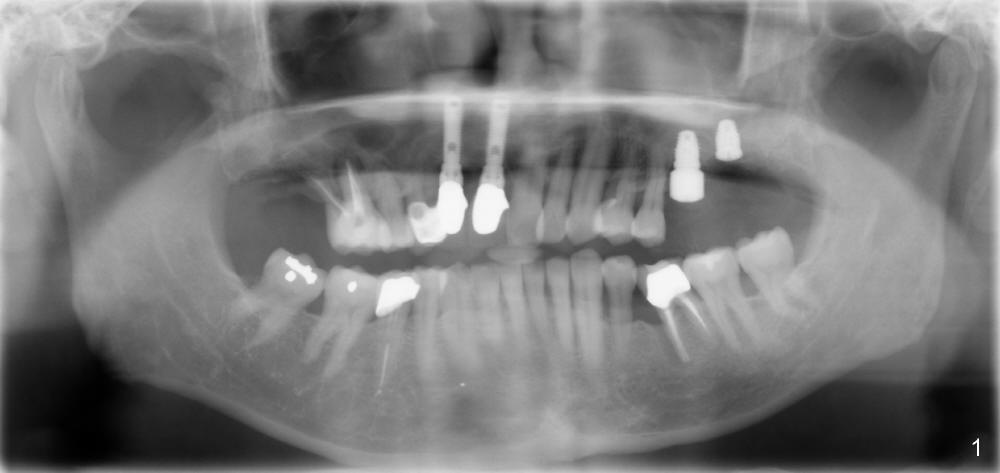

A 60-year-old man has poor dentition (Fig.1).  The tooth #3 is symptomatic with a mesiobuccal fistula.  PA shows large periapical radiolucency associated with the mesiobuccal root (Fig.2 *).  It appears that the tooth is non-salvageable.  The roots of this tooth are widely furcated.  The septum should be large unless destroyed by infection.